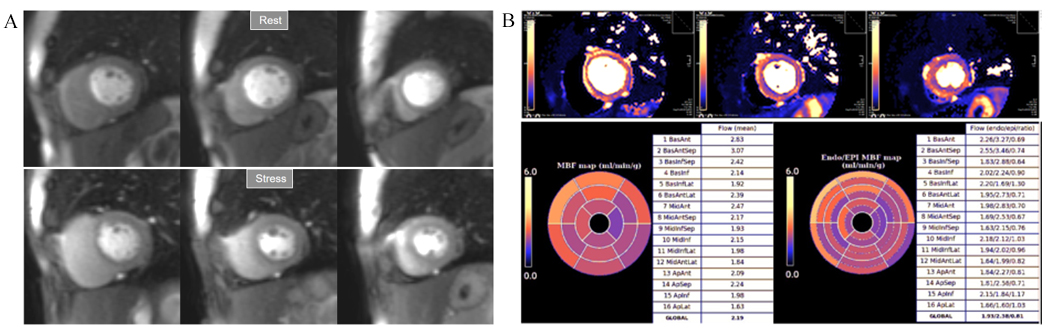

Fig. 32.Normal perfusion mapping. (A) Rest and stress perfusion studies showing absence of induced visual defect. (B) Normal global and segmental stress MBF.

Fig. 33.Mildly abnormal perfusion mapping. (A) Rest and stress perfusion studies showing absence of induced visual defect. (B) Mildly reduced global stress MBF (left table), particularly in the subendocardial regions (right table), suggesting MVD.